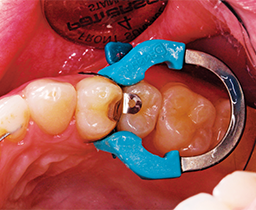

The contact was broken bucco-lingually and gingivally with the fender wedge in place (Fig. 3). The fender wedge was removed in order to evaluate the prep (Fig. 4).

Fig. 4 Fig. 5

The tooth was restored using a sectional matrix system in about six minutes (Fig. 5).